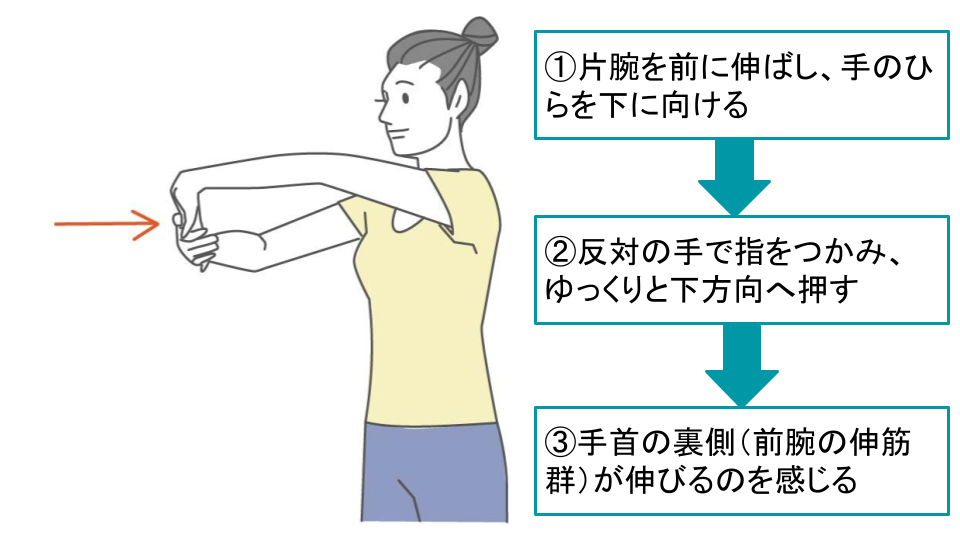

3-2.痛みを緩和させるためのストレッチ

手首や前腕の筋肉を柔らかくするためのストレッチを行うことで、肘の痛みの緩和が見込めます。

これらの筋肉が硬くなると、肘への負担が大きくなり、痛みが出やすくなるからです。

これから紹介するストレッチは、どれも簡単で、場所を選ばずにできます。整形外科での治療と並行して、あるいは、病院で具体的な治療を受けていない場合に、ぜひ試してみてください。

ただし、無理は禁物です!痛みを感じたらすぐに中止し、気持ち良いと感じる範囲で行いましょう。

■肘のストレッチ

■手首の伸展ストレッチ

■手首の屈曲ストレッチ |

いずれのストレッチも難しくはありませんが、以下のようなポイントを押さえておきましょう。

呼吸を止めない(ゆっくりと呼吸しながら行う)

反動をつけない(勢いをつけて行うと、筋肉を傷める可能性がある)

毎日続ける(1日に3〜4回、継続して行う)

痛みがある場合は中止(無理に行うと、症状が悪化する可能性がある)

ストレッチは、肘の痛みを和らげるのに役立ちますが、1回行っただけで劇的に痛みが消えるわけではありませんし、ストレッチだけで痛みが完全に治るわけでもありません。

毎日コツコツと続けることで、少しずつ痛みが和らいでいくことを目指しましょう。